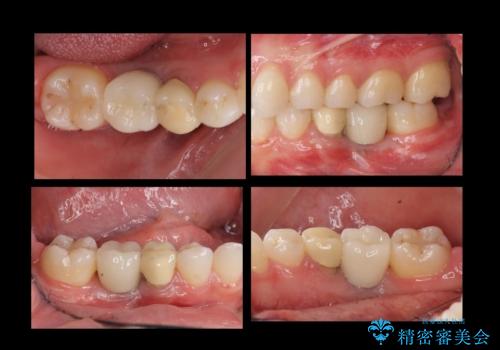

奥歯のインプラント

- 右下6番が保存不可能だったため、やむなく抜歯しました。

インプラント治療をご希望されたため、植立を行いました。

インプラントを入れる際、部分的に骨を増やす処置を行っています。